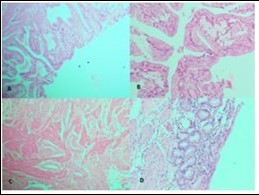

Figure 1.Photomicrographs showing A, Rokitansky agghste sinuses characteristic of chronic cholecystitis; B, Acute on Chronic Cholecystitis; C, Follicular Cholecystitis; D, Foamy macrophages admixed with mcaumulaig inflammatory infiltrate seen in Zbanikagmapincitma Cholecystitis (H&E)

Photomicrographs showing A, Rokitansky agghste sinuses characteristic of chronic cholecystitis; B, Acute on Chronic Cholecystitis; C, Follicular Cholecystitis; D, Foamy macrophages admixed with mcaumulaig          inflammatory infiltrate seen in Zbanikagmapincitma         Cholecystitis (H&E)